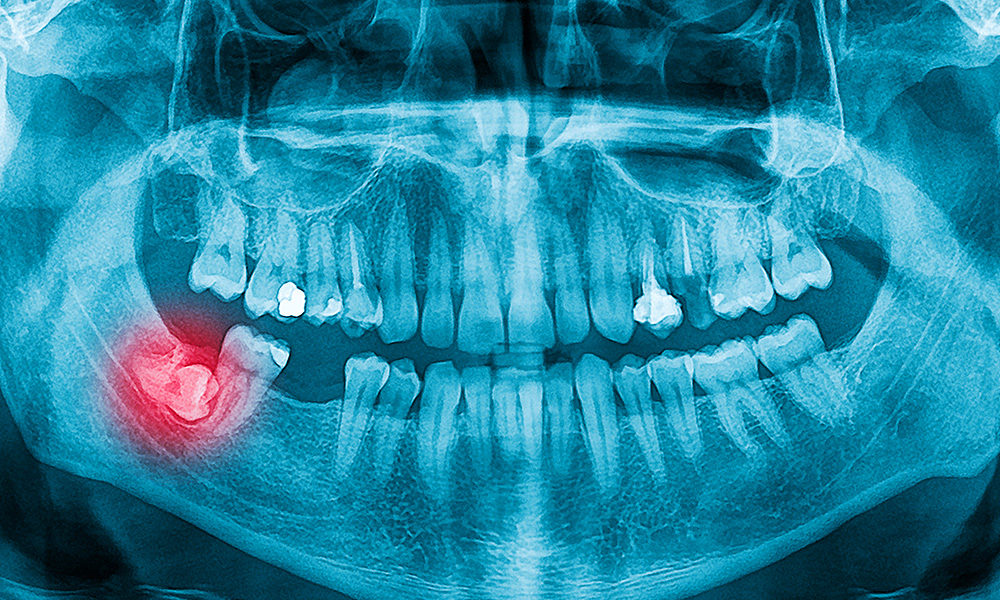

傾いて生えた親知らずを残しておくことで様々なリスクがあります。

一見健康に見えても部分的に歯周病を抱えている状態ですので早めの抜歯をおすすめします。

下あごの親知らずで注意しなければいけないのは親知らずの近くを通っている下歯槽神経と舌神経と呼ばれる2本の感覚神経です。

下あごの親知らずと神経の位置関係によっては注意しないと抜歯の際に神経の麻痺をおこすリスクがあります。

レントゲンで2次元的に下あごの親知らずとこの下歯槽神経が近そうな時はCT撮影をして立体的な位置関係を確認してから抜歯します。